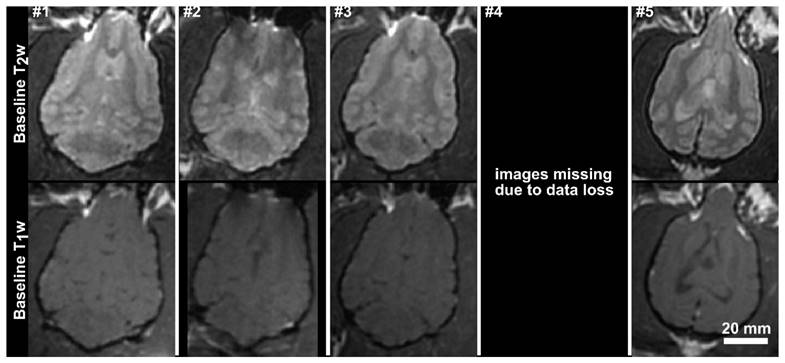

Fig 3

Baseline T1-weighted and T2-weighted axial MR images for the 5 subjects in the acute treatment group. The images for subjects 1, 2 and 3 have been resliced from oblique image stacks. The scale bar is 2 cm.

The MRI parameters used are summarized in Table 1. All treatments were performed under MRI-guidance at 3T (Signa MR750, GE Healthcare, Milwaukee, Wisconsin). Baseline T1 and T2 weighted images were obtained and are shown for group 1 in Fig.3. Contrast-enhanced (CE) T1 weighted imaging (0.1 ml/kg Gadovist) was used to assess the integrity of the BBB post-treatment, and post-treatment T2 and T2* images were used to identify edema or hemorrhage. Follow-up MR imaging was performed one week following the final treatment, using CE-T1, T2 and T2* weighted imaging. The follow-up imaging was performed on the same MRI scanner used during the treatments, except in one case where the system was unavailable and an alternate 3T platform was used (MAGNETOM Prisma, Siemens Healthcare, Erlangen, Germany).